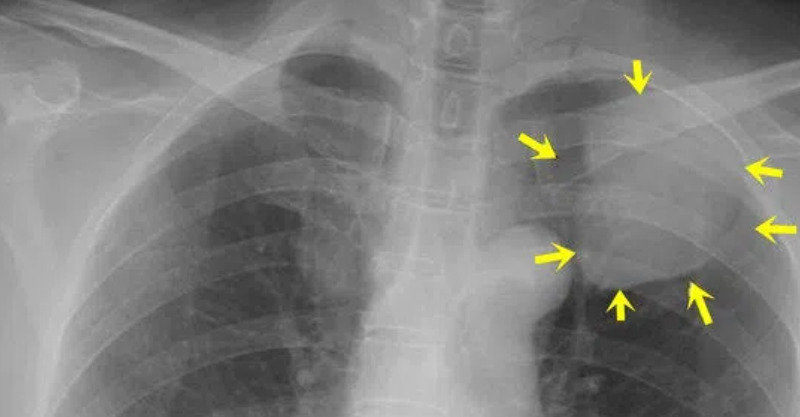

根據《東森新聞》報導,中華民國風溼病醫學會秘書長盧俊吉指出,紅斑性狼瘡的病徵相當多變,會逐步侵襲人體各個器官。此病症屬於人類自體免疫性疾病的一類,常見於育齡期女性,症狀則會依據個人體質而有所不同,容易發生病灶的部位包括皮膚、關節、中樞神經系統及腎臟等處。由於B細胞過度活化,製造出自體抗體來攻擊器官,造成長期慢性發炎反應,最終演變為多重器官系統的損壞。皮膚科醫師陳昱璁也提到,系統性紅斑性狼瘡好發於20到40歲女性,男女比約為1:9,其中皮膚表徵常是判別紅斑性狼瘡的重要關鍵。